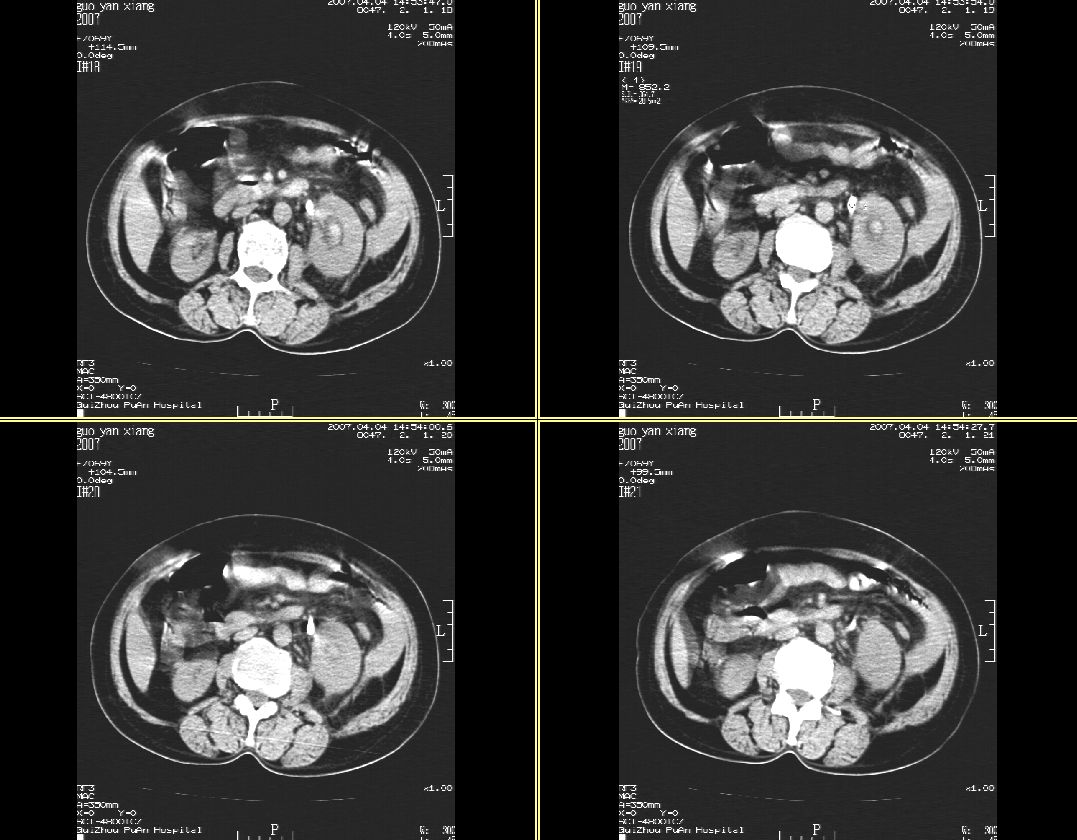

女性,59岁,腰痛,腹痛3天,未见肉眼血尿

左肾体弥漫性增大,肾周脂肪间囊密度增高,侧锥筋膜明显增厚,肾盂内见高密度影,左输尿管隐约可见,密度似较高,病程短,考虑:左肾急性肾盂肾炎,左肾盂内积血。不知临床还有没有其它相关体征及实验室检查?

肾周筋膜是增厚,肾盂内可见高密度影,但肾盂下部近输尿管处还是可见结石影。

左肾及输尿管上端结石。

支持:1、左侧输尿管上端结石伴肾盂积血、肾感染;

2、建议增强扫描进一步检查。

左肾及输尿管上端结石,伴左肾积水 积血。

左肾及输尿管上端结石伴肾盂积血、肾感染,建议增强.

支持:左肾及输尿管上端结石,伴左肾积水, 积血,合并感染.

左肾弥漫性增大,肾盂内见略高密度影,肾盂无明显扩张,肾实质密度均匀,肾周脂肪间囊密度增高,侧锥筋膜明显增厚,病程短,考虑:左肾急性肾盂肾炎,肾周感染,左肾盂内积血。建议完善相关检查或抗炎治疗后复查。